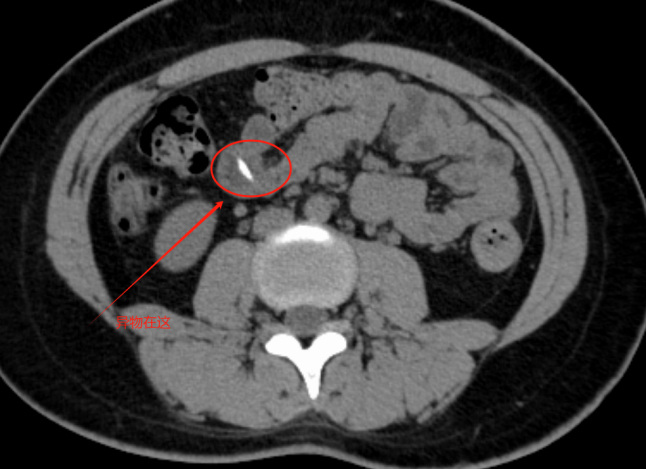

接诊的副主任医师张永祥详细询问病情后,安排她进行了腹部CT检查。结果显示,中腹小肠内有高密度影,高度怀疑是消化道异物在“捣乱”,门诊随即以“腹痛”将她收治入院。

管床医生卢嘉豪反复查看CT片,并仔细追问病史。许久之后,小刘才回忆起聚餐时吃了牛蛙。原来,一根约2厘米长、两端尖锐的棒状牛蛙骨,顺着食管、胃一路“闯”进了小肠,卡在了中后段小肠腔内,还刺入了肠壁黏膜。若不及时处理,很可能引发小肠穿透性损伤,导致肠穿孔、消化道出血、腹腔感染等严重后果,后果不堪设想。

手术当天,麻醉团队为小刘实施全身麻醉后,崔东明医生团队在她的脐部皱褶处开了一个小切口,建立器械操作通道。经过仔细探查,在回肠中段发现了那根长约2厘米的牛蛙骨头,它横刺于小肠两侧壁,邻近肠壁充血水肿明显。手术团队用钳子完整取出异物,这根牛蛙骨的惊险人体之旅就此画上句号,手术顺利完成。